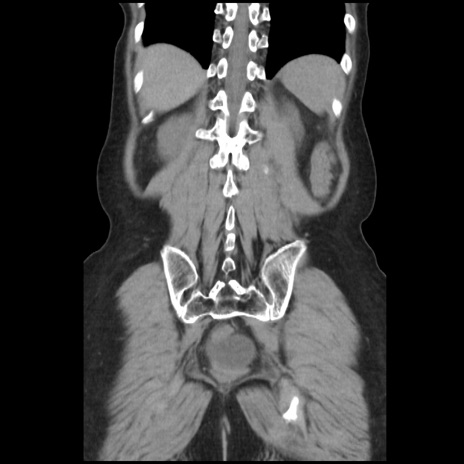

症例32(冠状断像)

【症例】40歳代 女性

【主訴】上腹部痛、嘔気・嘔吐

【現病歴】約9時間前頃から急に上腹部痛、嘔気、嘔吐が出現。改善しないため救急要請。

【既往歴】子宮頚癌(広汎子宮全摘術、放射線療法)、腸閉塞

【身体所見】腹部:平坦、軟、腸雑音亢進、上腹部を中心に腹部全体に圧痛あり。

【データ】WBC 8400、CRP 0.03